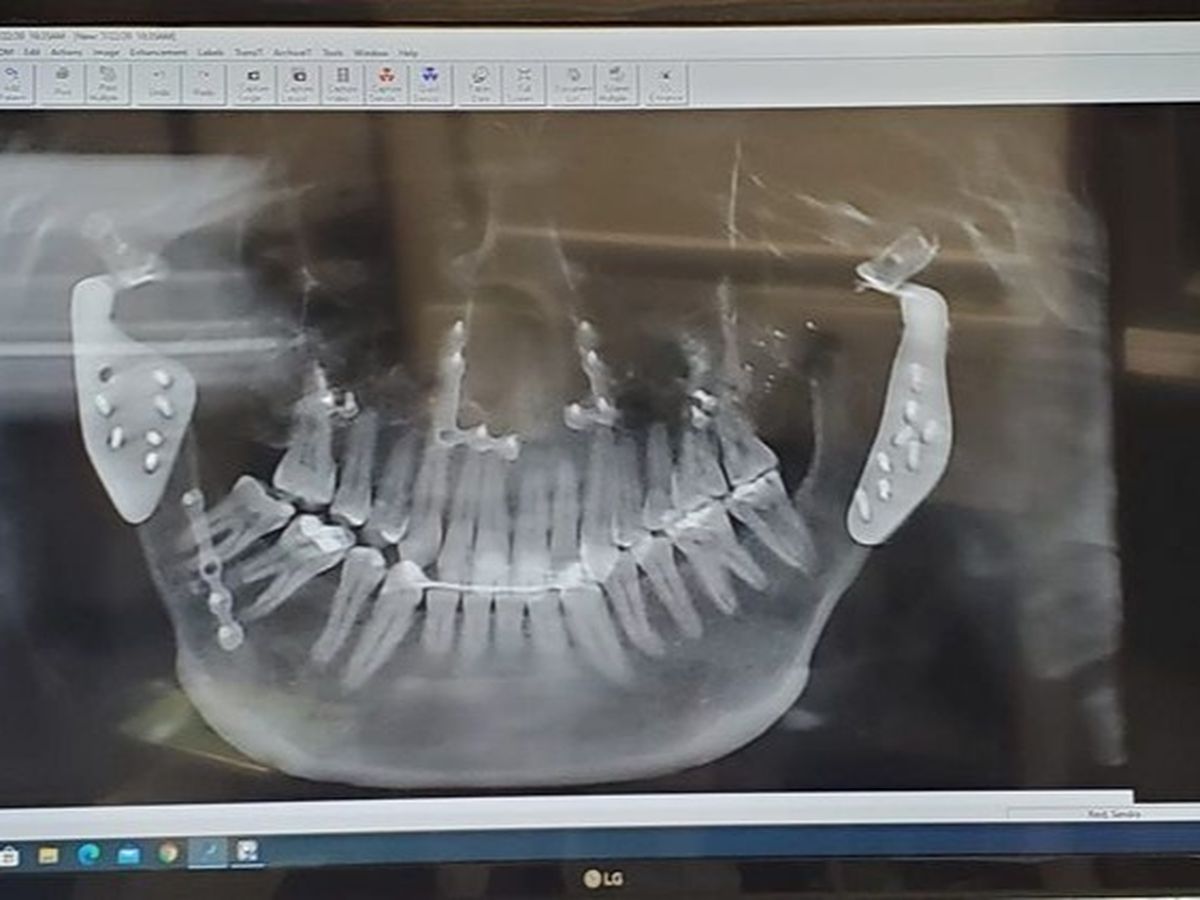

Where do I even begin? I'll start by saying that my chronic debilitating pain started out as TMJ with condibular degeneration; an osteostritic condition. The fact is that despite all the good intentions, I found myself a product of bad luck, bad genes, and bad doctors. I am in pain ALL day. This type of severe jaw pain interfers with my eating, communication, thinking and ability to live. I struggle with shooting nerve pain, white hot pain when eating or talking, a salivary gland syndrome called Frey Syndrome, Central Sensitivity, headache, immobility of my right eyebrow from lame nerve, and an undiagnosed sunlight induced salivary gland spasm and cramp like eating something VERY sour. I learned early on, at age 13, that behaving as a mute due to pain, only got you trampled. I have always lamented that my Dad and Stepmom's commitment to my health, is the only reason I even survived. I learned I had to "wear a mask" to disguise my pain; a sad thing to learn so young. What you see on the outside, is my greatest attempt to hide my suffering from your awareness. My big smile is usually what one will notice about me first, but that smile comes with a great cost. This mask I wear, to hide my pain, has grown very tiresome, and I am working to stop this character flaw. It's sad to decide that after so long, this is the year I lose my smile. Fast forward 20 years, countless specialist, 8 surgeries (the last 4 done at the Mayo Clinic in Rochester, MN), and I am left in sever pain with no end in sight. I live at a pain level of 8, and I am out of medical options at only the age of 32 (as per the Mayo Clinic). Last year I completed two surgeries; to remove my hemi-joints (partial jaw joint replacements) to take a CT scan of my empty anatomy, to then fabricate and place my prosthetic jaw joints, that were placed 3 months after. I have found zero relief, and in fact now I have a new pain (white hot pain where my prosthetic is), in addition of new nerve pain. My Mayo Clinic doctor, Dr F, didn't seem to like the results of my surgery, he told me he had never seen a patient with "new" pain and he referred me back to my general doctor, who then told me he isn't qualified to care for me. My patient images were even archived frkm my mobile access, before even the one year mark of my last surgery. I have exhausted every avenue, or so I thought. I finally found something that helps, Deep Laser Therapy at a place called PainFree Life Centers in Troy, MI (85 miles from my home). I heard of it from word of mouth, a family member has found success with it, and she insisted I try it as well. During my first treatment, it felt like the laser was sewing my prosthetics in place. The second appointment, the ache was missing in my maxillary arch, from my two previous double orthognathic surgeries. By the fifth visit, I had actual change in my nerve function/ feeling. Headaches I didn't even know I had, went away. Halfway through my treatments, I started gaining movement in my face, I haven't had function to in roughly 16 years! The laser has even shrunk the size of a cyst I have in my maxillary jaw. Although this is all good news, I am still not able to eat without the white hot pain. I have yet to find a food worth the pain. Without regular laser treatments (4 per week), I seem to decline drastically. I have already completed my expected 40 treatments, and I have paid for 40 more. As time goes on, we are seeing that this may need to be a life-long maintenance for me, in order to have any kind of quality of life. The owner of PainFree Life Centers has said that he would sell me one of his 40K lasers, for $25,000, in order to do life-long treatments at home. It is really hard to ask for this, I am not one to have my hand out. All of the money from this will go directly to paying for this laser, as a part of what seems to be my ticket to life. To anyone who donates, it means the world to me. There isn't much life outside of this pain, and I have so many more years ahead of me, I just don't want the rest of them to be this painful. Day in and day out. It never stops. I just keep chugging forward, because that's all you can really do. Thank you